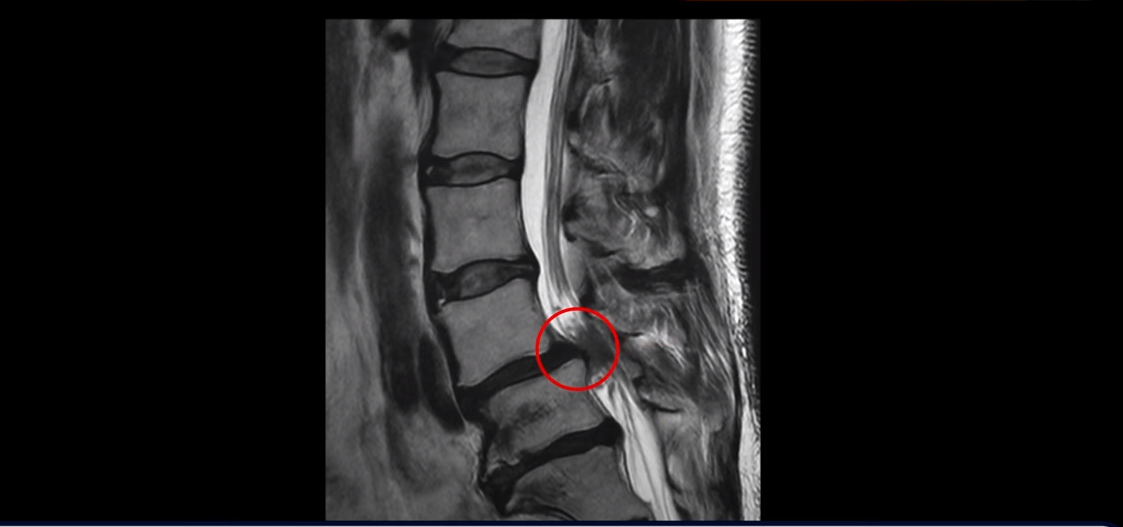

제가 먼저 이 환자분 MRI를 보면서 설명 드린 후 이분 말씀 더 들어보겠습니다. 보시다시피 두 마디가 심하게 퇴행되어 있고

4번 5번에는 척추뼈가 밀려나간 전방전위증이 있습니다.

4번 5번에 심한 중심성 협착도 있습니다.

전방전위증이 있는 분들은 뼈가 밀려 나가 있으므로 다른 사람들에 비해 협착이 더 빨리 더 쉽게 올 수 있습니다. 이분도 나이가 48세라는 젊은 나이인걸 고려하면 협착이 다른 분들에 비해 매우 빠르게 왔다고 볼 수 있습니다.

양쪽 신경 가지가 빠져 나가는 추간공도 왼쪽 오른쪽 모두 좁아져 있습니다.

5번 1번에는 가운데로는 디스크가 밀려나와 있습니다.

이건 아주 오래된 퇴행성디스크로 보입니다. 그래서 이 환자분은 양쪽 엉덩이와 다리가 모두 저리고 아픈 게 양쪽 추간공 문제 때문일 수도 있고 중심성 협착 때문일 수도 있습니다. 퇴행성디스크 때문에 아플 가능성은 상대적으로 적어보입니다.